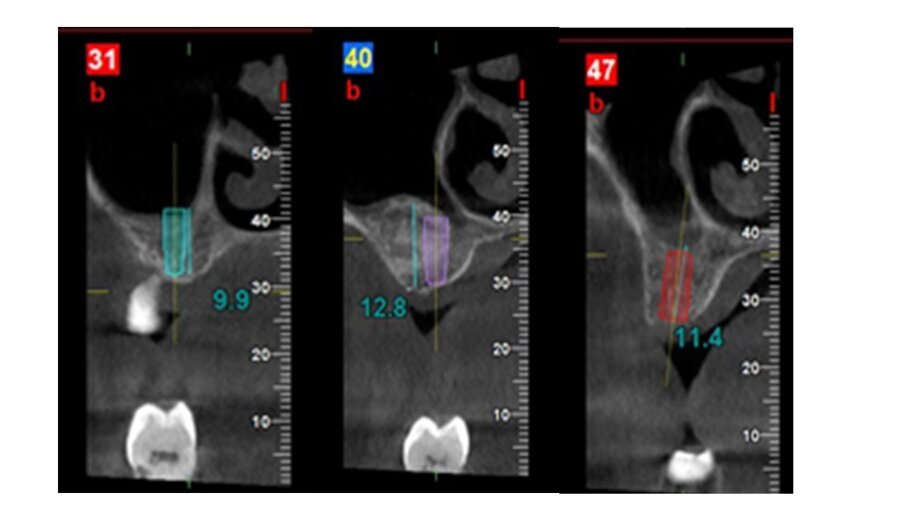

Una paziente donna di 63 anni, con osteoporosi ed ipotiroidismo, si presenta con assenza del 16 e 17, richiedendo riabilitazione dentale fissa. Si procede con l’esecuzione della CBCT per avere dettagli maggiori. Dall’analisi della CBCT nell’area edentula si misura un’altezza ossea verticale <5 mm in zona 16-17 e si nota la presenza di una lesione periapicale dell’elemento dentale 15 (Figg. 1-3). Quindi si programma l’intervento per l’estrazione del 15 e l’intervento per l’esecuzione del rialzo del seno mascellare con approccio laterale, con uso di osso bovino collagenato e spugnette di fibrina, al fine di ottenere l’incremento di osso verticale6. Dopo 5 mesi dall’esecuzione del rialzo di seno mascellare si esegue CBCT di controllo, per verificare l’effettivo aumento di osso verticale e programmare l’inserimento implantare (Figg. 4, 5).

A 5 mesi dall’intervento dal rialzo del seno mascellare con approccio laterale, grazie alla CBCT è stato possibile valutare la presenza di osso verticale. Si è visto che nell’area rigenerata si è avuto un incremento dell’osso, che presenta un range da 8 a 12 mm circa. Quindi verificata una rigenerazione verticale è possibile una riabilitazione implantare della zona 16, 17 e 15 con la scelta di impianti di lunghezza e un diametro adeguato (Figg. 4, 5)7, 8.